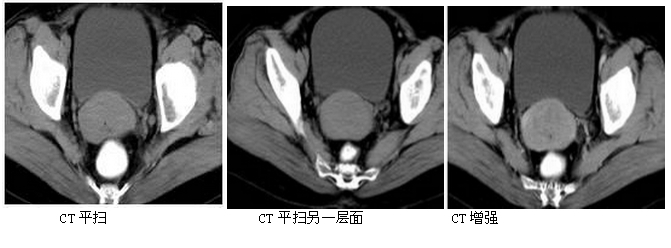

女,49岁,阴道不规则流血伴流水样物2月余。 宫颈癌(病理诊断)。诊断依据:①CT示宫颈增大,边缘不规则,可见中等密度的肿块; ②MRI示宫颈处肿块,T1WI呈稍低或等信号,T2WI多较正常宫颈信号高;③增强扫描后可见不规则或均匀强化。④结合临床阴道不规则流血伴流水样物2月病史可诊断。鉴别诊断:宫颈肌瘤。子宫肌瘤一般边界清晰,包膜完整,呈膨胀性生长。